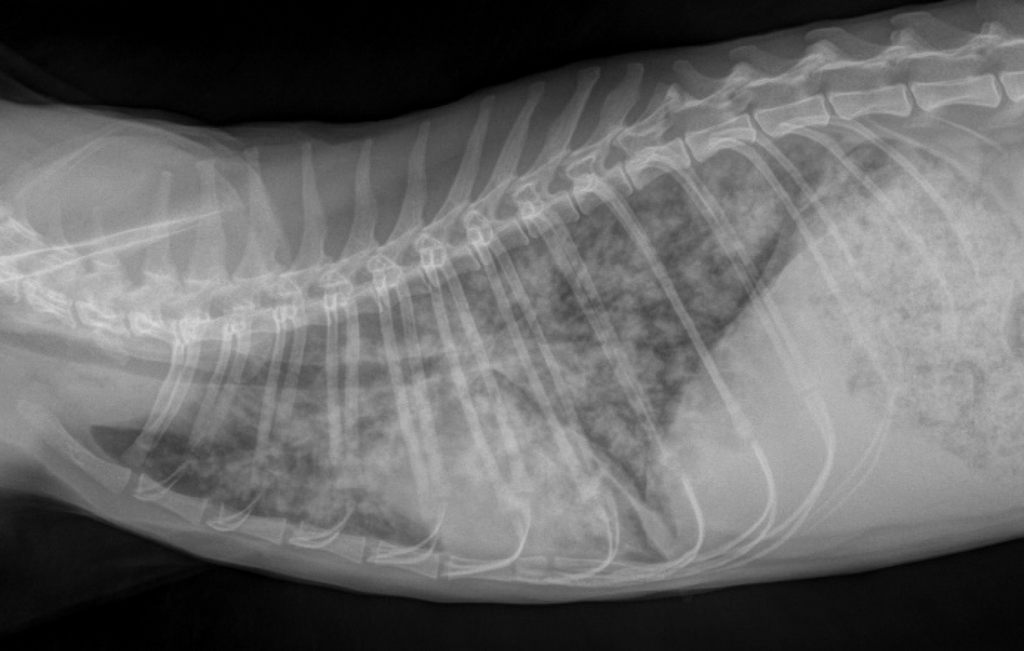

Symptome sind je nach Schwere und Art des Lungenwurmbefalls leichter bis starker Husten bis hin zur Atemnot. Als Folgeschaden einer Infektion mit „Angylostrongylus vasorum“ kann ein Rechtsherzversagen auftreten. Erste Hinweise auf eine Infektion kann bereits ein Röntgenbild des Brustkorbes ergeben – hier erkennt man deutliche Hinweise auf eine mehr oder weniger starke Entzündung der Bronchien (Bronchitis).